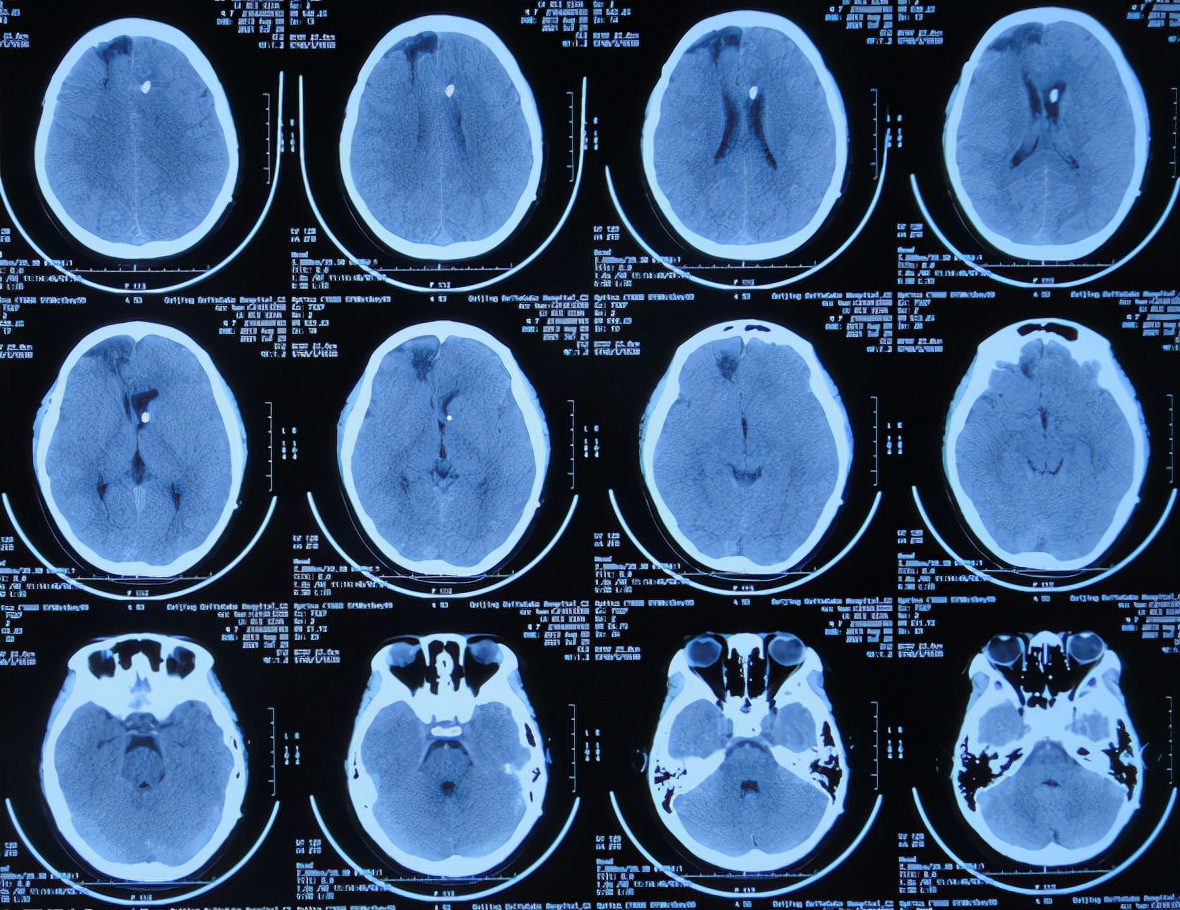

腰大池引流术后3天即2021年4月2日,脑脊液白细胞仍高,患者仍持续发热,查脑CT示仍有积水和水肿( 图-4 )。

图-4: 2021年4月2日脑CT

腰大池引流术后7天即2021年4月6日,体温降低至37.6℃,查脑CT示脑室缩小( 图-5 );遂拔除了腰大池引流管。

图-5: 2021年4月6日脑CT

但第2次腰大池引流术后2天即2021年4月9日,体温仍未下降(持续在38.6-39.0℃波动),查脑CT示脑室再次扩张( 图-6 );且脑脊液化验白细胞反而升更高,脑脊液逐渐浑浊,给予更改抗生素。

图-6: 2021年4月9日脑CT